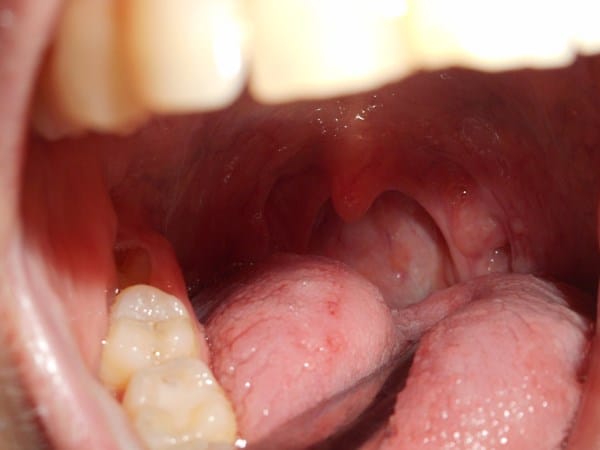

Os mando la foto, para ver si alguien podría ayudarme a saber que podría ser.

Acudo a ustedes porque ya no sé que hacer, os cuento un poco mi problema desde mayo del año pasado empecé con este "calvario", y es que llevo desde ese tiempo me sale el moco muy blanco y seco además tengo la sensación de tener algo dentro de la nariz(en la parte final de ella sobre todo en la fosa izquierda), y me baja hacia la garganta ya que sólo tengo una amígdala inflamada la izquierda. He ido al otorrino y me comento que en la fosa izquierda tengo rinitis hipertrófica y también degeneración polipoide de cornete medio de FNI, me mando una analítica de alergia porque se pensaba que era alérgica a algún alimento y fuera el causante de que mi amígdala izquierda estuviera inflada y el resultado fue que salió negativo, pero como soy alérgica a polvo, al polen, a los pelos de gatos y demás me dijo que el creía que fuese de alergia al polvo así que me mandó vacunas para ello y un spray nasal Dymista y me comentó que me mirara el digestivo a ver si podía ser reflujo y fuera el causante de tener al amígdala así. Tengo cita con él para Octubre de este año.

Así que fui al digestivo y me hizo una endoscopia y un esofagograma y el resultado fue que me salió algo de reflujo pero que no era la causa de ello, así que cada día que pasa estoy peor, ya que noto en mi garganta como si tuviese algo que no se baja y cada día la amígdala más inflamada.